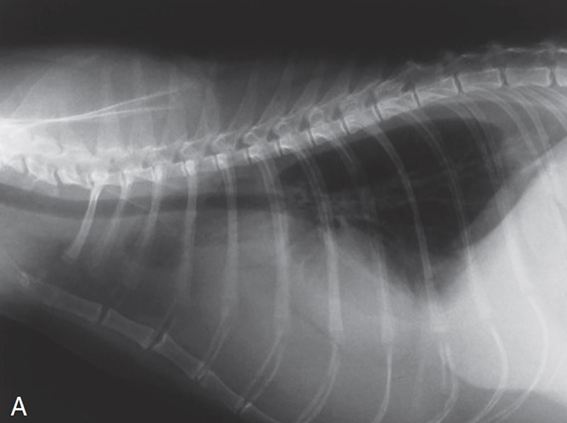

![]() | Pneumothorax - 폐가 쪼그라들면서 하얗게 보임 - 심장이 떠 있음 |

![]() | Pneumomediastium - 종격동에도 공기가 참 - 평소 안 보이던 식도, 대동맥 가지, 전대정맥 등도 보임 - 하얀 화살표는 흉관 tube를 장착해 놓은 것 - 임상적으로 큰 의의는 없음 - 종양 때문에 넓어질 때가 가장 많음. 비만일 수도 있음. |